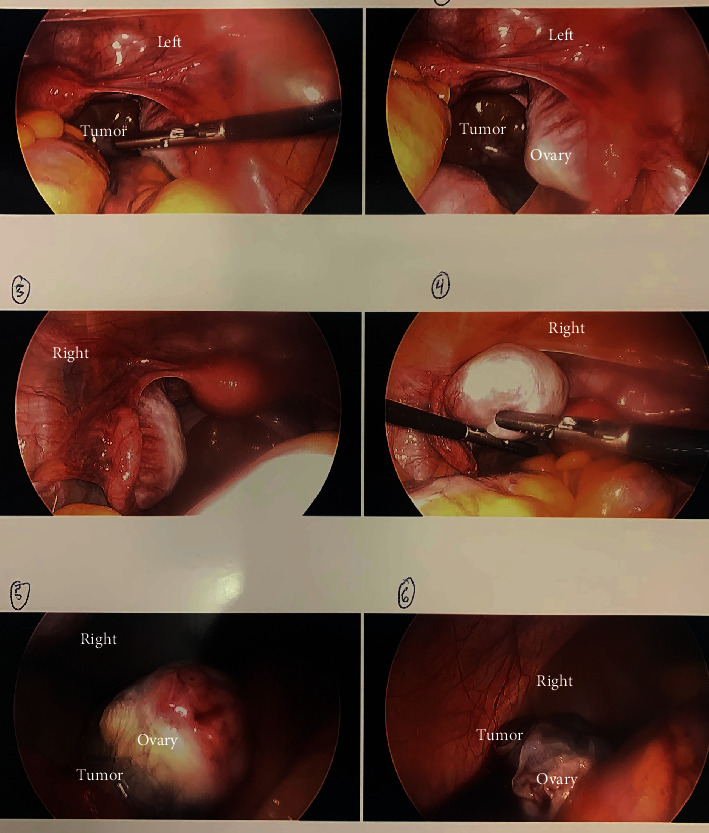

Background: Anti-NMDA receptor (A-NMDAR) encephalitis is an autoimmune condition often associated with ovarian teratoma. Surgical removal of the teratoma is generally curative, and recurrence is uncommon. Case: A 14-year-old female presented with psychiatric symptoms and was ultimately diagnosed with A-NMDAR encephalitis during a prolonged hospitalization. She was found to have bilateral ovarian teratomas, underwent laparoscopic bilateral ovarian cystectomy, and returned to neurologic baseline within 2 months. One year later, the patient was re-presented with similar symptoms and was diagnosed with recurrent A-NMDAR encephalitis. Initial imaging was negative for ovarian teratomas. After another prolonged hospitalization, repeat imaging ultimately demonstrated a suspected left ovarian teratoma. A left salpingo-oophorectomy was performed, and the patient's condition again fully recovered. Conclusion: This case of A-NMDAR encephalitis presented with many atypical features including neuropsychiatric presenting symptoms, bilateral teratomas, and severe recurrence of disease. While imaging is the recommended modality for investigation of etiology, no teratoma was identified on the second presentation, leading to an ethical and clinical conundrum in this adolescent patient. More research is needed to investigate other diagnostic methods for A-NMDAR encephalitis without distinct teratoma on imaging in female patients.

Abstract Image